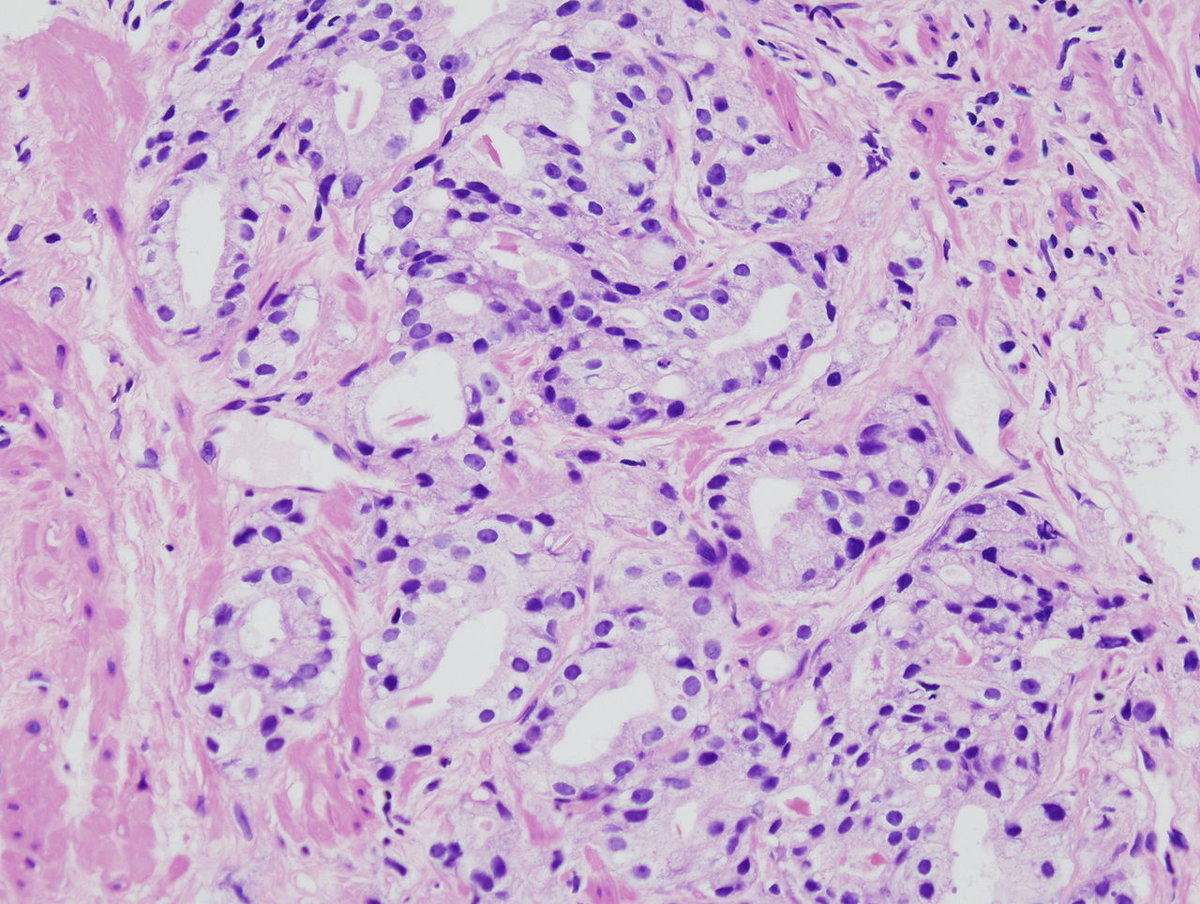

©wikipedia.org/KGH, CC BY-SA 3.0

© wikipedia.org/Alex brollo, CC BY-SA 4.0

© wikipedia.org/Alex brollo, CC BY-SA 3.0